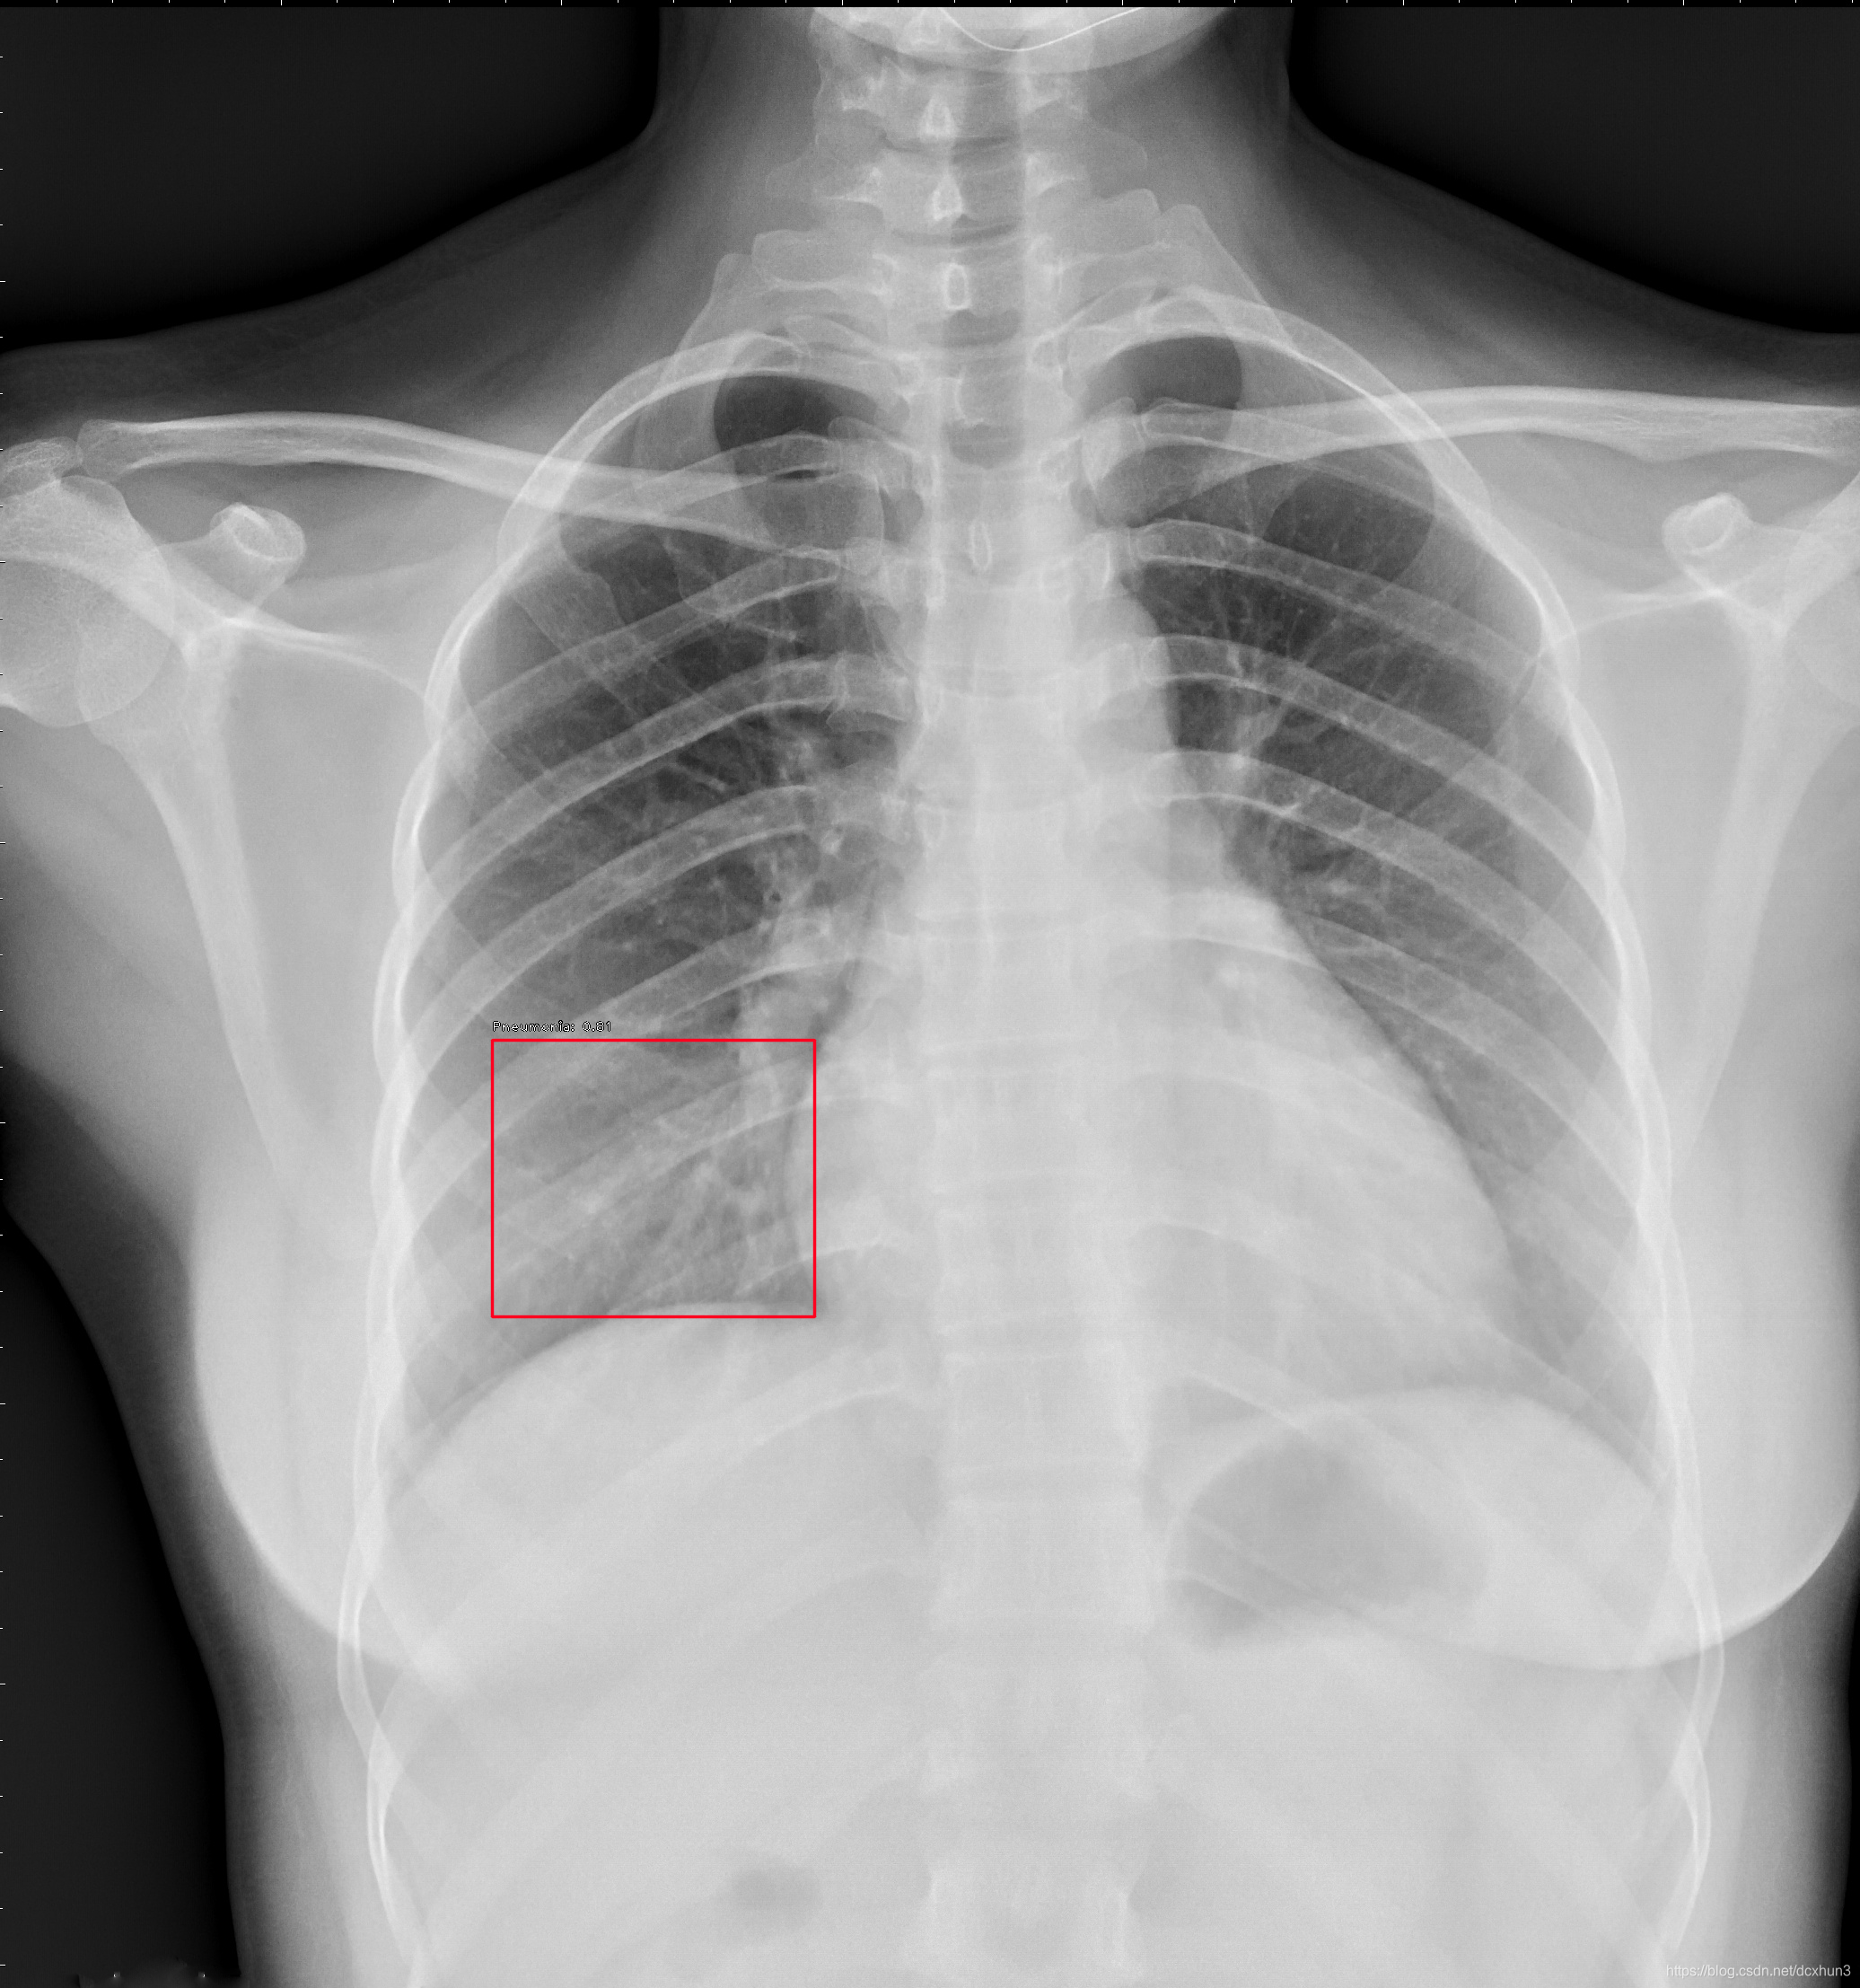

训练了一批肺炎数据,目前最好的指标如下:

> val数据

> num_fp=2.0, num_tp=337.0 340 instances of class Pneumonia with

> average precision: 0.9911 mAP: 0.9911

>

> test数据

> num_fp=2.0, num_tp=33.0 35 instances of class Pneumonia with

> average precision: 0.9343 mAP: 0.9343

效果图

若要真正达到临床使用,还有很多路要走